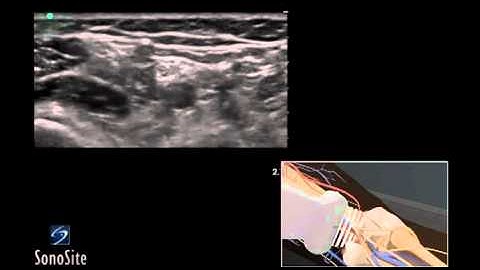

Fundamentals of US-Guided Nerve Blocks - Needling Phase [Part 2/2]